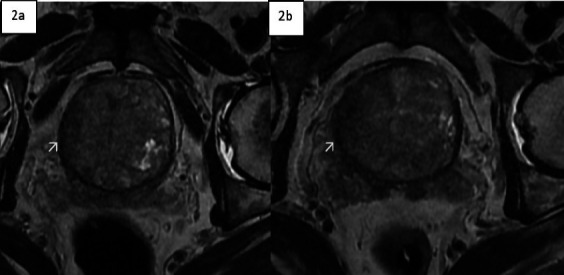

Case presentation: A 69-year-old male was referred to Tikur Anbessa Specialized Hospital (TASH) with obstructive lower urinary tract symptoms (LUTS) lasting seven months. He had previously undergone transurethral resection of the prostate (TURP), with histopathological findings suggestive of benign prostatic hyperplasia (BPH). Further investigation revealed an extremely elevated PSA level of 1768 ng/ml. Magnetic Resonance Imaging (MRI} raised high suspicion for locally advanced prostate cancer; however, a repeat biopsy and histopathology ultimately diagnosed TB prostatitis. The patient responded successfully to anti-tuberculosis therapy.